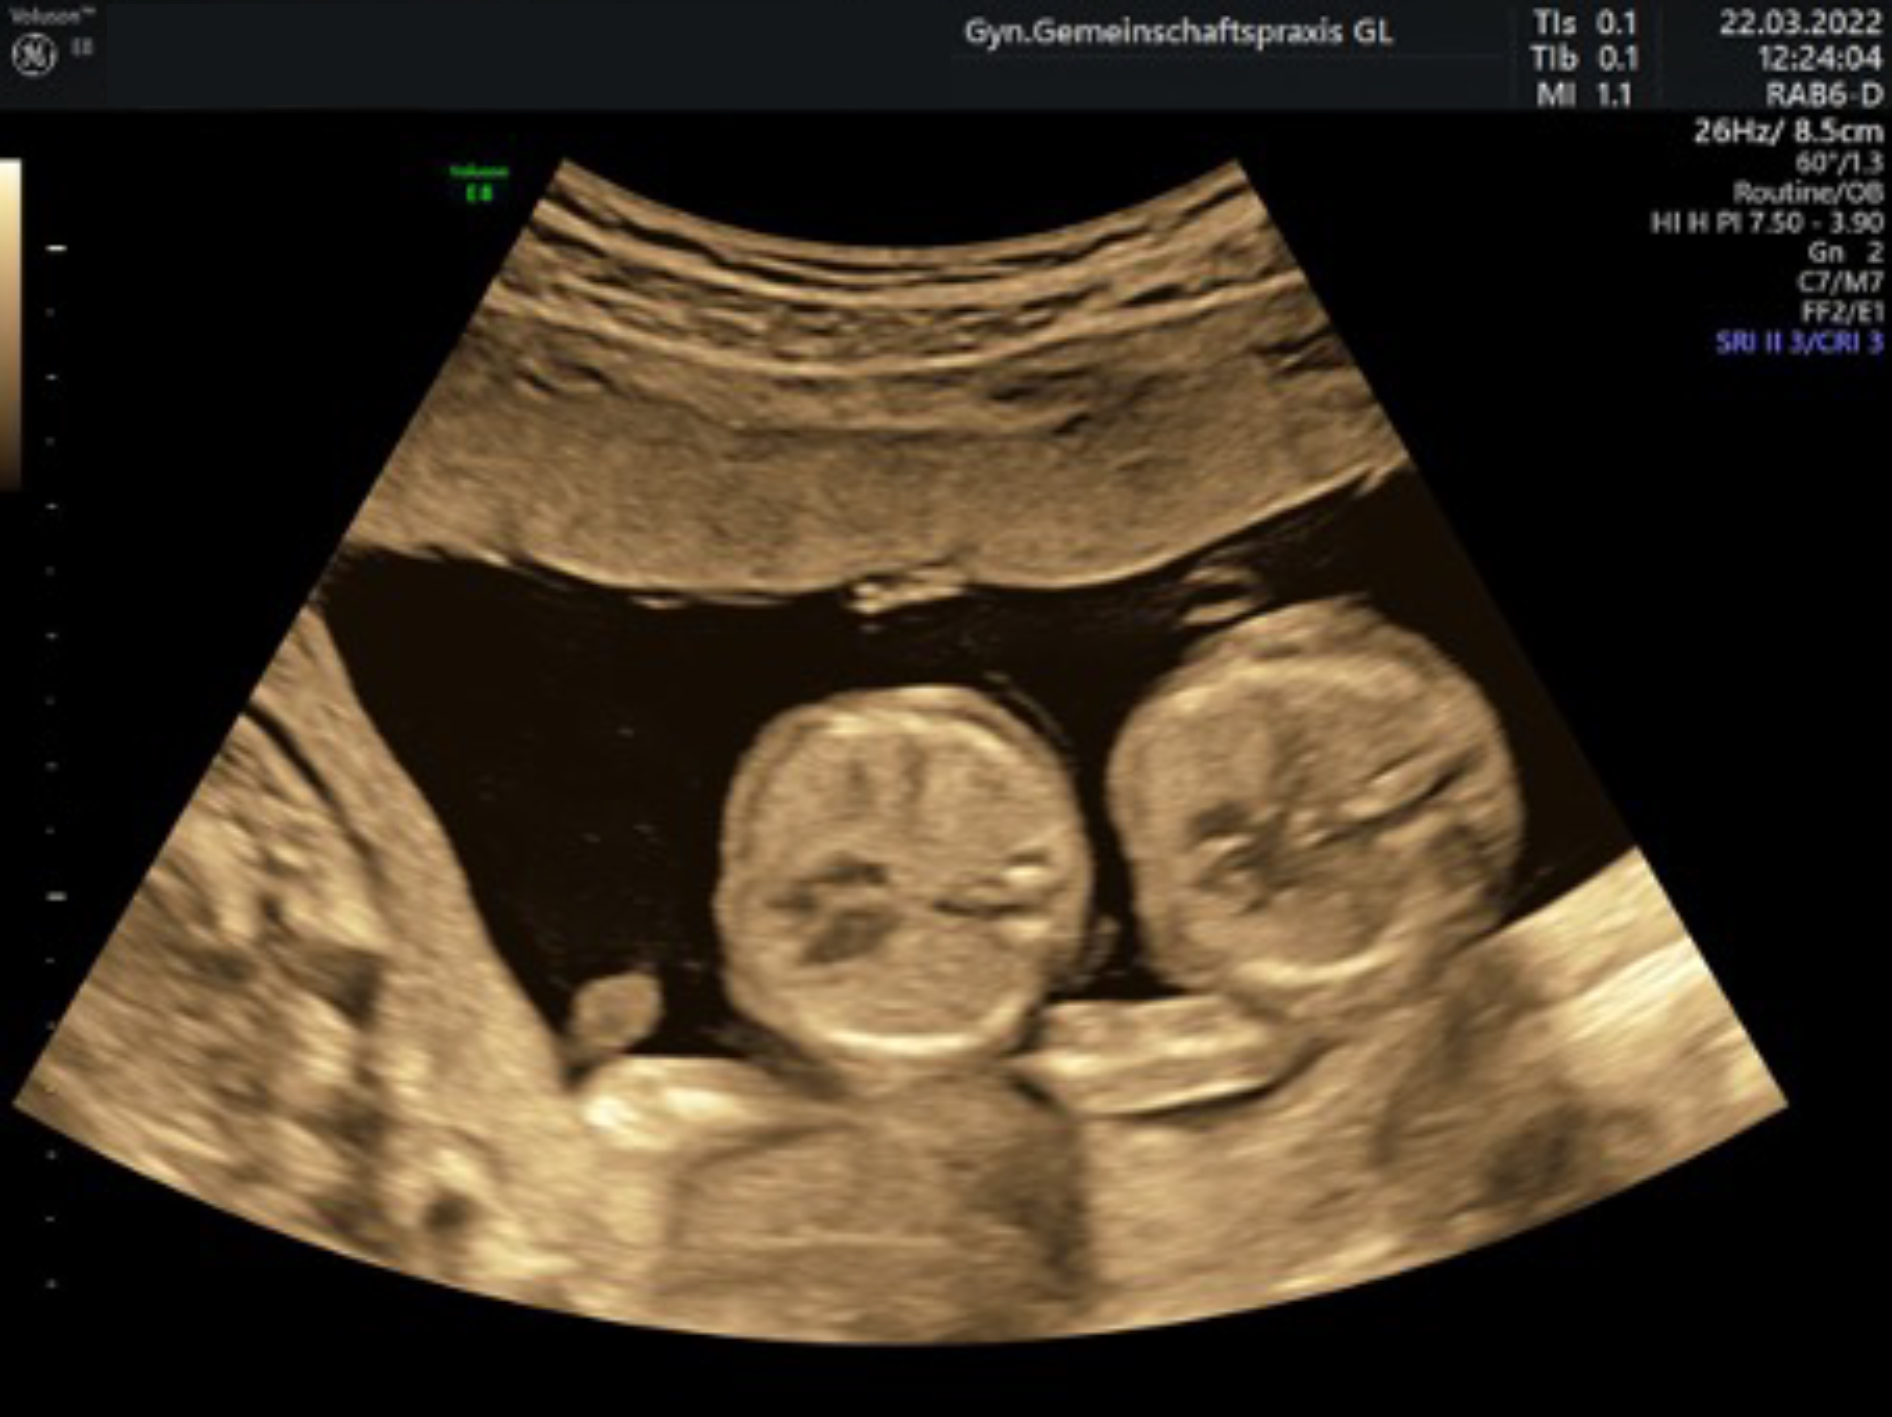

Bei Mehrlingsschwangerschaften wird die invasive Diagnostik für jedes Kind einzeln durchgeführt.

Für Mehrlingsschwangerschaften ist der NIPT z Zt nicht sinnvoll nutzbar.

Bei besonderen Indikationen (ab 35 J, Mehrlinge, best. Vorerkrankungen, kranken Kindern in der Vorgeschichte oder der Familie, schlechten Sichtbedingungen oder kindl. Auffälligkeiten) wird die sog. Organdiagnostik durchgeführt.